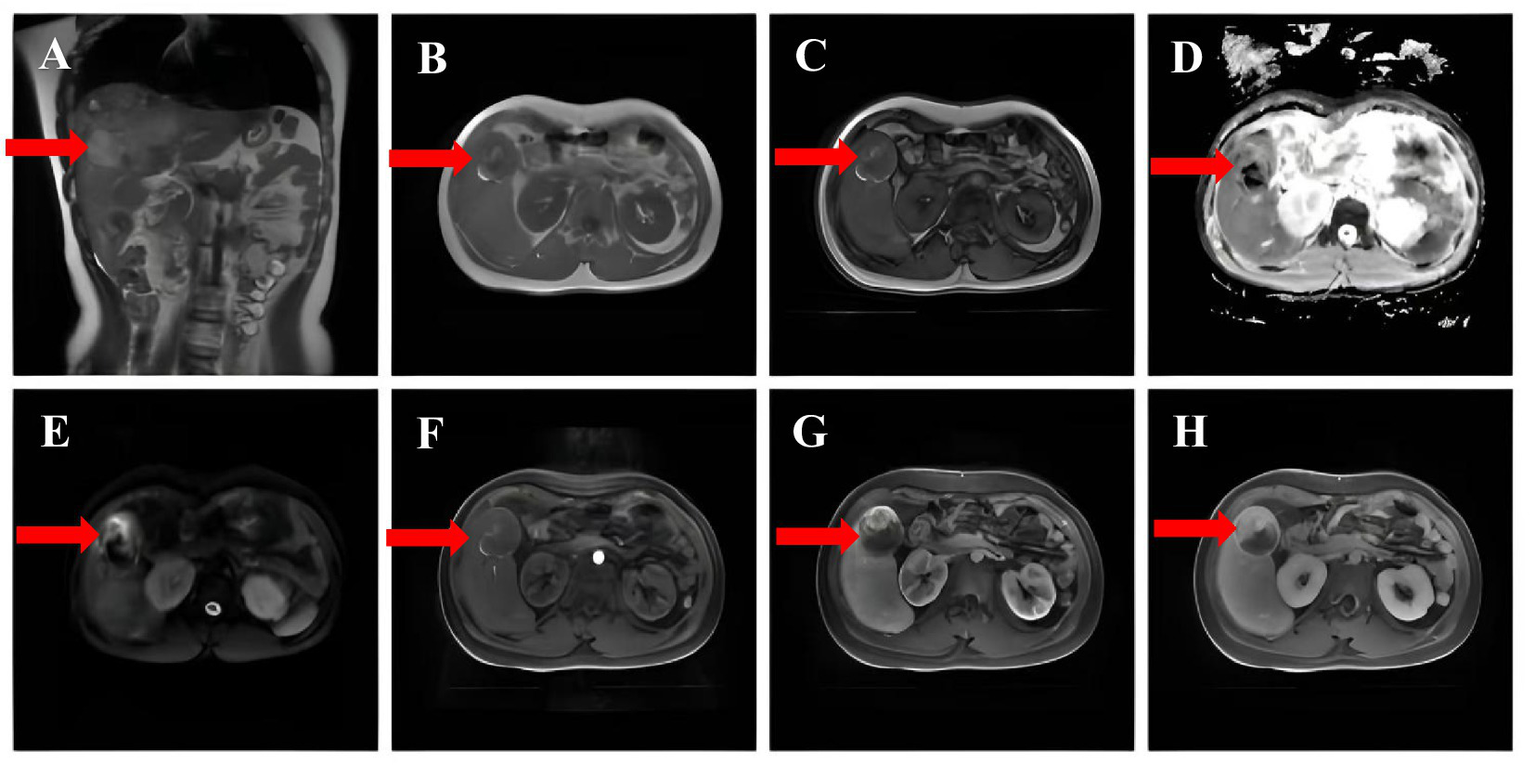

Figure 2

(A) Fast echo spin (FSE) showing mixed hypointense signals. (B,C) No significant signal reduction in the same inverse phase was observed. (D,E) DWI and ADC revealed no significant diffusion restriction. (F,G,H) Contrast-enhanced MRI scans with delayed phase enhancement.

Complementary examinations: A routine blood test revealed a platelet (PLT) count of 36.00 × 109/L (reference range: 125–350 × 109/L). Liver function tests showed levels of alanine aminotransferase (ALT) of 43 U/L (7–40 U/L), aspartate aminotransferase (AST) of 32 U/L (13–35 U/L), and Y-glutamyltranspeptidases (y-GT) of 158 U/L (7–45 U/L). Kidney function assessment demonstrated a serum creatinine level of 100.5 μmol/L (41–81 μmol/L). Coagulation studies revealed D-dimer levels of 4.01 mg/L (0–0.5 mg/L). The alpha-fetoprotein (AFP) content was normal and serum levels of protein induced by vitamin K absence or antagonist II (PIVKA-II) were 271.44 U/mL (0–40 ng/mL). Hepatitis virus markers, including hepatitis B and C, were negative. Targeted genetic testing for metabolic disorders was not performed. Contrast-enhanced computed tomography of the upper abdomen disclosed multiple iso-low mixed density foci in the liver. The largest lesion measured about 5.7 cm in diameter, with ill-defined borders. A number of lesions displayed segregation-like changes and inhomogeneous enhancement after enhancement, with CT values of 49–78 H (Figures 1A–C). Hepatobiliary contrast-enhanced MRI showed that the liver was obviously enlarged, with multiple, irregular prolonged T1 and slightly prolonged T2 signals. On diffusion-weighted imaging (DWI), some of the lesions showed restricted dispersion and the arterial phase of the dynamic enhancement scan displayed a ring shape. A dynamic enhancement scan showed ring-shaped and nodular mild enhancement in the arterial phase, progressive enhancement in the portal phase, and signal reduction in the delayed phase. Additionally, curved long T1 and long T2 signal shadows were observed in the perihepatic and peri-splenic areas (Figure 2). On December 11, 2024, due to the presence of liver lesions of unknown etiology, the patient’s guardian expressed a willingness to cooperate fully in order to establish a clear diagnosis, the patient underwent hepatic puncture biopsy (right anterior lobe of the liver) under local anesthesia. Despite the administration of Atriplopa prior to the procedure, the platelet count remained below 50 × 109/L and did not reach the target threshold. Histological analysis revealed a proliferative hepatocellular lesion with moderate differentiation, structural disorder, and localized pseudo-glandular ductal structures. The immunohistochemistry profile was as follows: GPC-3 (−), GS (+), Hsp70 (+), Arg-1 (−), HepPar-1 (hepatocyte +), CD34 (vascular +), CK19 (bile duct +), Ki-67 positivity 5%, β-catenin (nuclear +), CD10 (+), and special reticulofibrillary staining (+). These findings were consistent with a diagnosis of β-catenin-activated hepatocellular adenoma.

Follow-up: The patient and guardian exhibited poor adherence, reappearing only 4 months later. Laboratory panels showed a further drop in platelet count relative to pre-treatment values. A CT scan of the upper abdomen revealed a marked reduction in lesion size 4 months after the procedure (Figure 1D). Due to financial constraints, the guardian chose to stop romiplostim and start avatrombopag again. The patient is also taking oral traditional Chinese medicine prescribed by another institution. Close outpatient surveillance is ongoing.